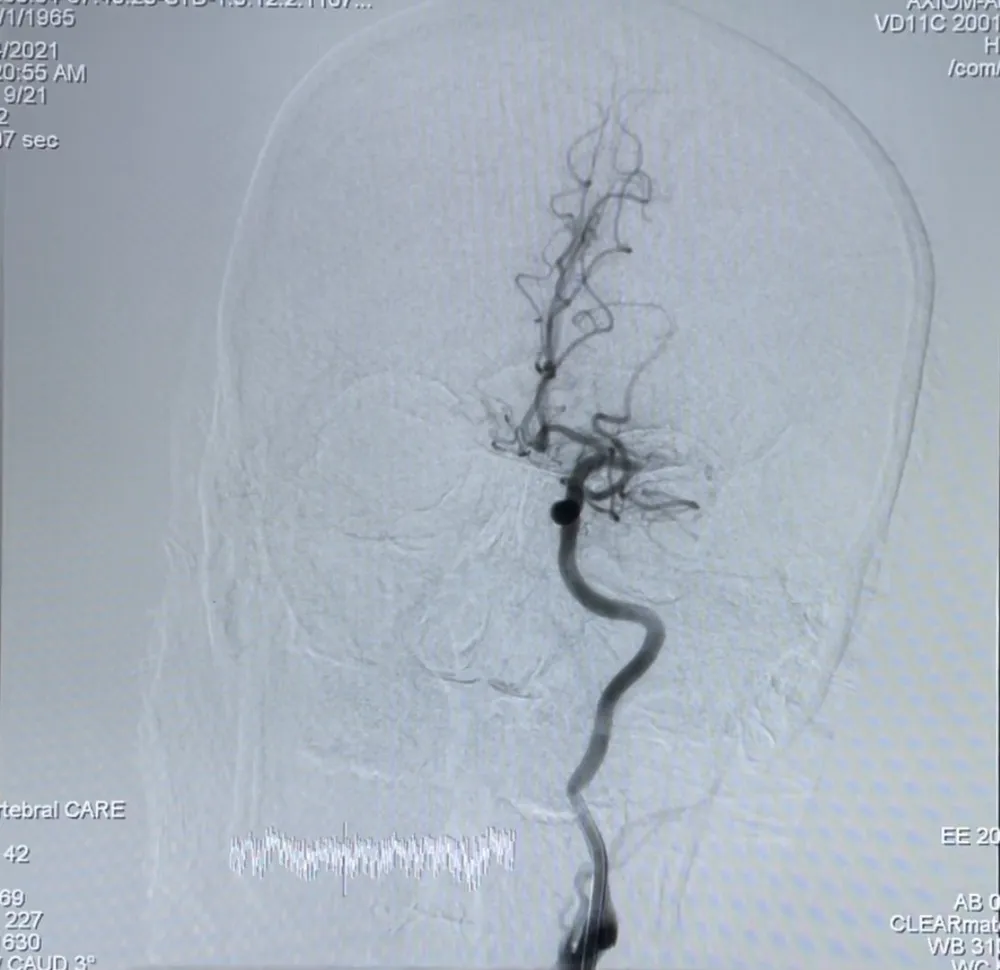

Tại đây, BV đã lập tức báo động khẩn cấp Code Stroke (báo động đột quỵ) và tiến hành hội chẩn khẩn ngay tại khoa cấp cứu.Trong tình hình dịch bệnh COVID-19 đang điễn biến phức tạp, nhưng các BS vẫn khẩn trương làm theo quy trình, đẩy nhanh xét nghiệm COVID-19, toàn bộ ê kíp tuân thủ sử dụng các phương tiên phòng hộ cá nhân. Qua Chụp CT, các bác sĩ phát hiện bệnh nhân bị tắc hoàn toàn động mạch não giữa phía bên trái đoạn gốc.

Bệnh nhân bị tắc hoàn toàn động mạch não giữa phía bên trái đoạn gốc. Ảnh: BVCC

Thiếu tá bác sĩ Tạ Vương Khoa cùng ekip tiến hành điều trị bắt cầu tiêu sợi huyết và can thiệp mạch để lấy huyết khối bằng dụng cụ cơ học. Quá trình chụp mạch não, ghi nhận tổn thương huyết khối tắc hoàn toàn đoạn gốc trên nền hẹp xơ vữa nặng. Ekip nhanh chóng lấy huyết khối bằng Stent và nong bóng đoạn gốc động mạch não giữa bên trái. Sau khi can thiệp đã tái thông mạch,kết thúc can thiệp bệnh nhân tỉnh liệt nửa người bên phải đã được cải thiện, sau can thiệp chưa ghi nhận các tổn thương mới